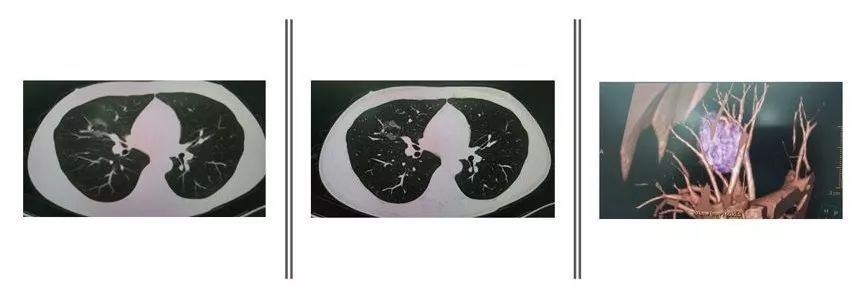

肺小结节三维重建CT平扫

这是我院放射科专门针对肺内小结节开设的检查项目,有更小的层距,一般为小于2mm,而且使用较新的多排HRCT,因此对肺小结节的分辨率更高。除此之外,还有其他特点:

① 可以更精确测定肺小结节的密度,根据C/T比值来确定肺小结节为纯磨玻璃结节,混合磨玻璃结节,还是实性结节。

② 可以观察肺小结节与血管的关系,血供对肺小结节良恶性判断很有价值。

③ 可以计算肺小结节的体积,计算结节倍增时间,这也是良恶性判断的依据。

④ 可以通过计算机得到三维立体成像,直观地观察结节形态,边缘,血管症等良恶性判断指标。

(左图常规CT,中图HRCT,右图3D重建)

⑤ 可以通过特殊软件重建结节与气管及血管的关系,对结节定位有极高应用价值,是精准解剖性肺段切除术的有力保障。

CT的层距越小,对于判断肺小结节的大小更精确,请看下图。